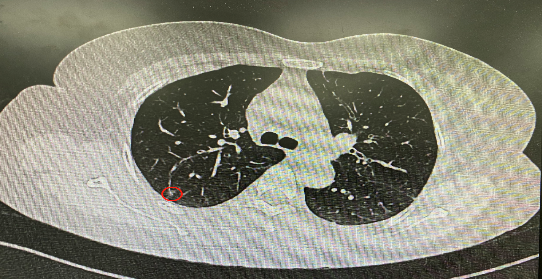

今年54歲的李女士(化名)7月初突然出現(xiàn)右上部腹痛,起初并未在意,以為稍作休息就會好轉(zhuǎn),但疼痛卻并未消退,持續(xù)了一個星期。李女士實在難以忍受,才在家人陪伴下來到西安國際醫(yī)學(xué)中心醫(yī)院就診。胸外科二病區(qū)崔凱主任接診患者后,詳細詢問病情并查閱檢查資料,經(jīng)胸部HRCT檢查,結(jié)果提示:右肺上葉后段混合密度結(jié)節(jié)影,考慮原位癌可能,即將患者收入胸腔外科二病區(qū)住院治療。

經(jīng)與患者家屬溝通,崔凱主任決定行外科手術(shù)治療。為達到精準(zhǔn)切除,術(shù)前需進行肺小結(jié)節(jié)切除前定位。由于結(jié)節(jié)位于右肺上葉后段,傳統(tǒng)經(jīng)胸外穿刺術(shù)無法抵達病灶。崔凱主任與呼吸內(nèi)科一病區(qū)歐陽海峰主任討論后,決定擬行LungPro全肺診療導(dǎo)航下染色定位。即術(shù)前通過Lung Pro導(dǎo)航規(guī)劃染色位置,經(jīng)Lung Pro實時引導(dǎo)支氣管鏡抵達既定位置,注入亞甲藍染色劑標(biāo)記結(jié)節(jié)位置。

使用術(shù)前規(guī)劃系統(tǒng)重建全肺3D模型,并于外科醫(yī)生討論染色位置,最終確定標(biāo)記染色點—右肺上葉后段b亞段(RB2b)。術(shù)中使用P290(4.9mm外徑)標(biāo)準(zhǔn)支氣管鏡,根據(jù)導(dǎo)航術(shù)前規(guī)劃路徑,Lung Pro實時導(dǎo)航下,GS鞘管進入RB2b遠端官腔外病灶并注射亞甲藍染色劑。

一切準(zhǔn)備就緒,7月15日,崔凱主任團隊聯(lián)合歐陽海峰主任團隊為患者行單孔胸腔鏡下右肺上葉后段切除術(shù),手術(shù)用時128分鐘順利完成。進入胸腔后,亞甲藍染色部位明顯,患者發(fā)生癌變的右肺上葉后段被成功切除。術(shù)后標(biāo)本根據(jù)染色部位迅速找到結(jié)節(jié),剖開位置兼染色位置和病灶完全符合,行術(shù)中冰凍后快速送病理檢查。經(jīng)術(shù)后病理檢查,明確診斷為(右肺上葉)原位腺癌。